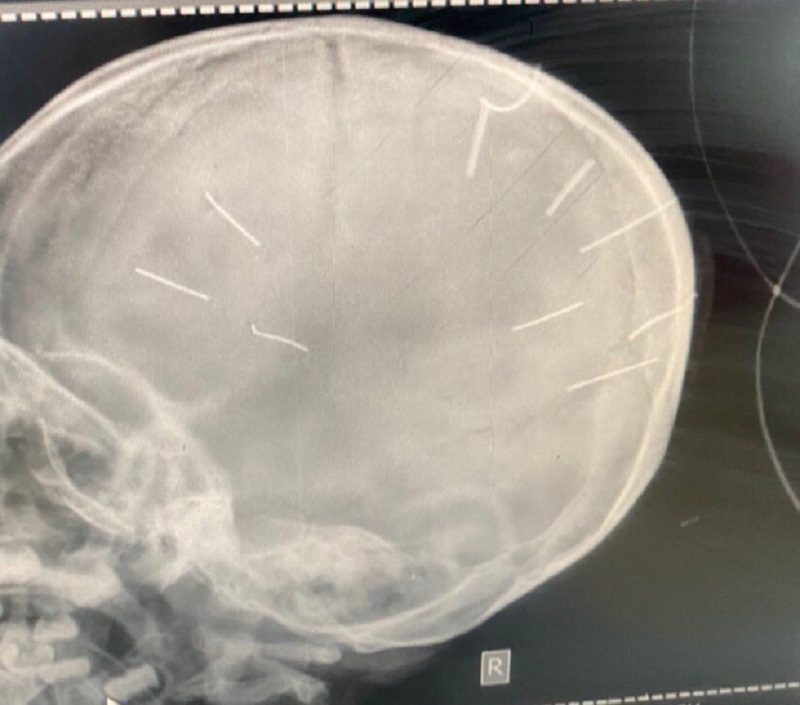

![]() |

| Hình ảnh 9 chiếc đinh trong hộp sọ cháu bé - Ảnh: BVCC |